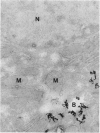

Polymeric myeloma IgA, labelled with 125I, was injected intravenously into rats that were killed 5, 30, or 60 min later and the livers removed, fixed and sectioned. Autoradiographs of ultra-thin sections examined in the electron microscope showed that the IgA first became bound to the plasma membrane of the hepatocytes but after 30 min much of it was transported across their cytoplasm and became localized around the bile canaliculi. At this time, autoradiographs of 1 micrometer sections examined in the light microscope showed the contents of the bile ducts in the portal tracts to be labelled heavily. These results confirm the previous finding of rapid transport of IgA across the liver and show directly that the hepatocytes are the cells that carry it out. No intracellular organelle or vesicular structure, discernible within the resolving power of the techniques used, could be implicated in the transport mechanism.